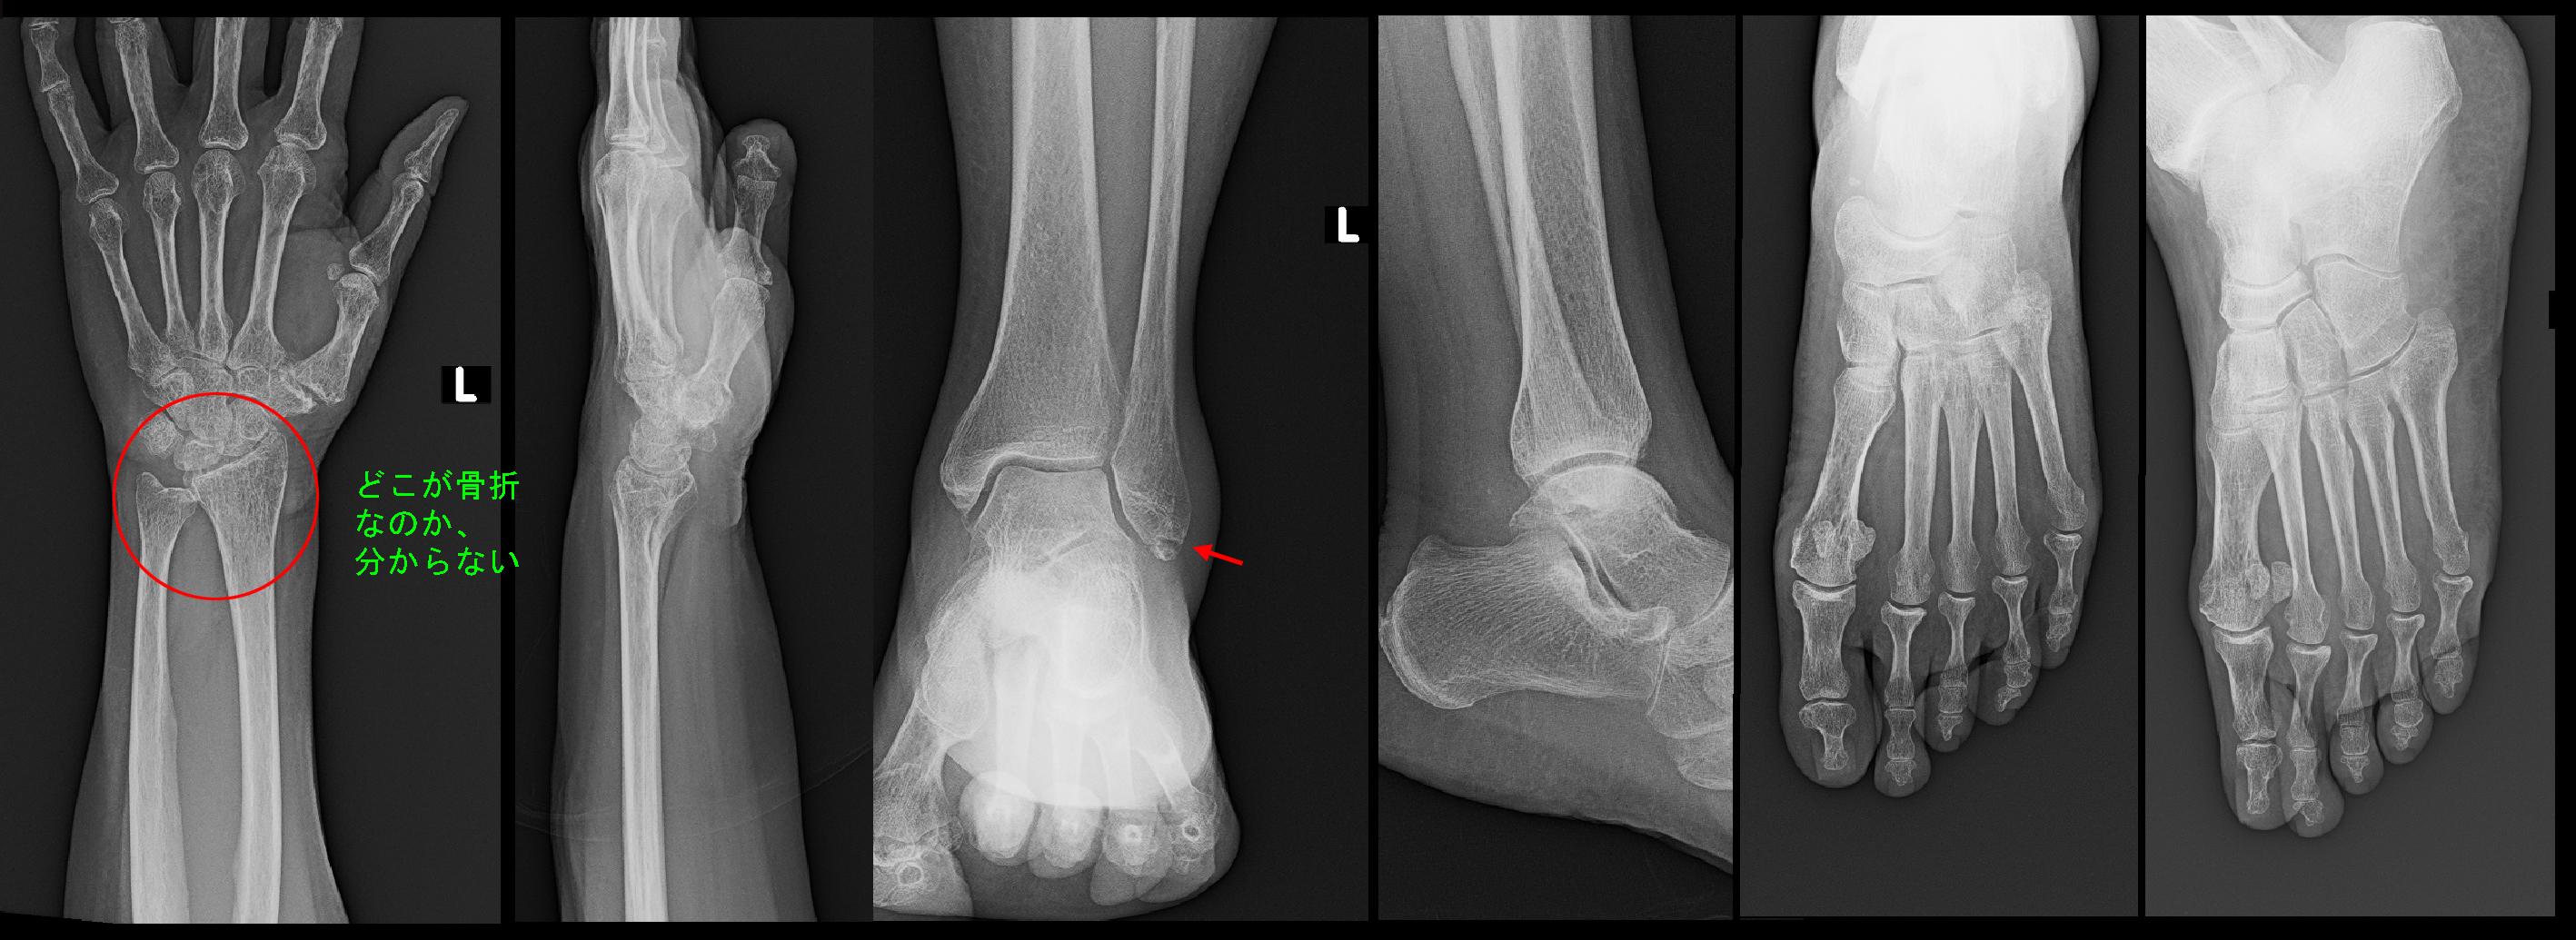

76才の無職の女性です。令和5年8月5日に1か月前からの腰痛で受診され、神経根ブロックという注射の治療で症状は軽減しています。8月16日腰痛が再発して受診されましたが、いっしょに2週間前からの右足背部痛の相談を受けました。見た目にも右足は腫れていて、皮膚色も赤みを帯びています。

76才女 初診時指針.jpg

患者さんは腰痛のためにあまり動かないようにしていたと言っていました。下図の赤丸が痛みの領域です。圧痛は第2第3中足骨に認めました。経過からは全くおかしいのですが、中足骨の疲労骨折を疑います。

76才女 Xp1.jpg

当然ですが、レントゲン像は異常はありません。